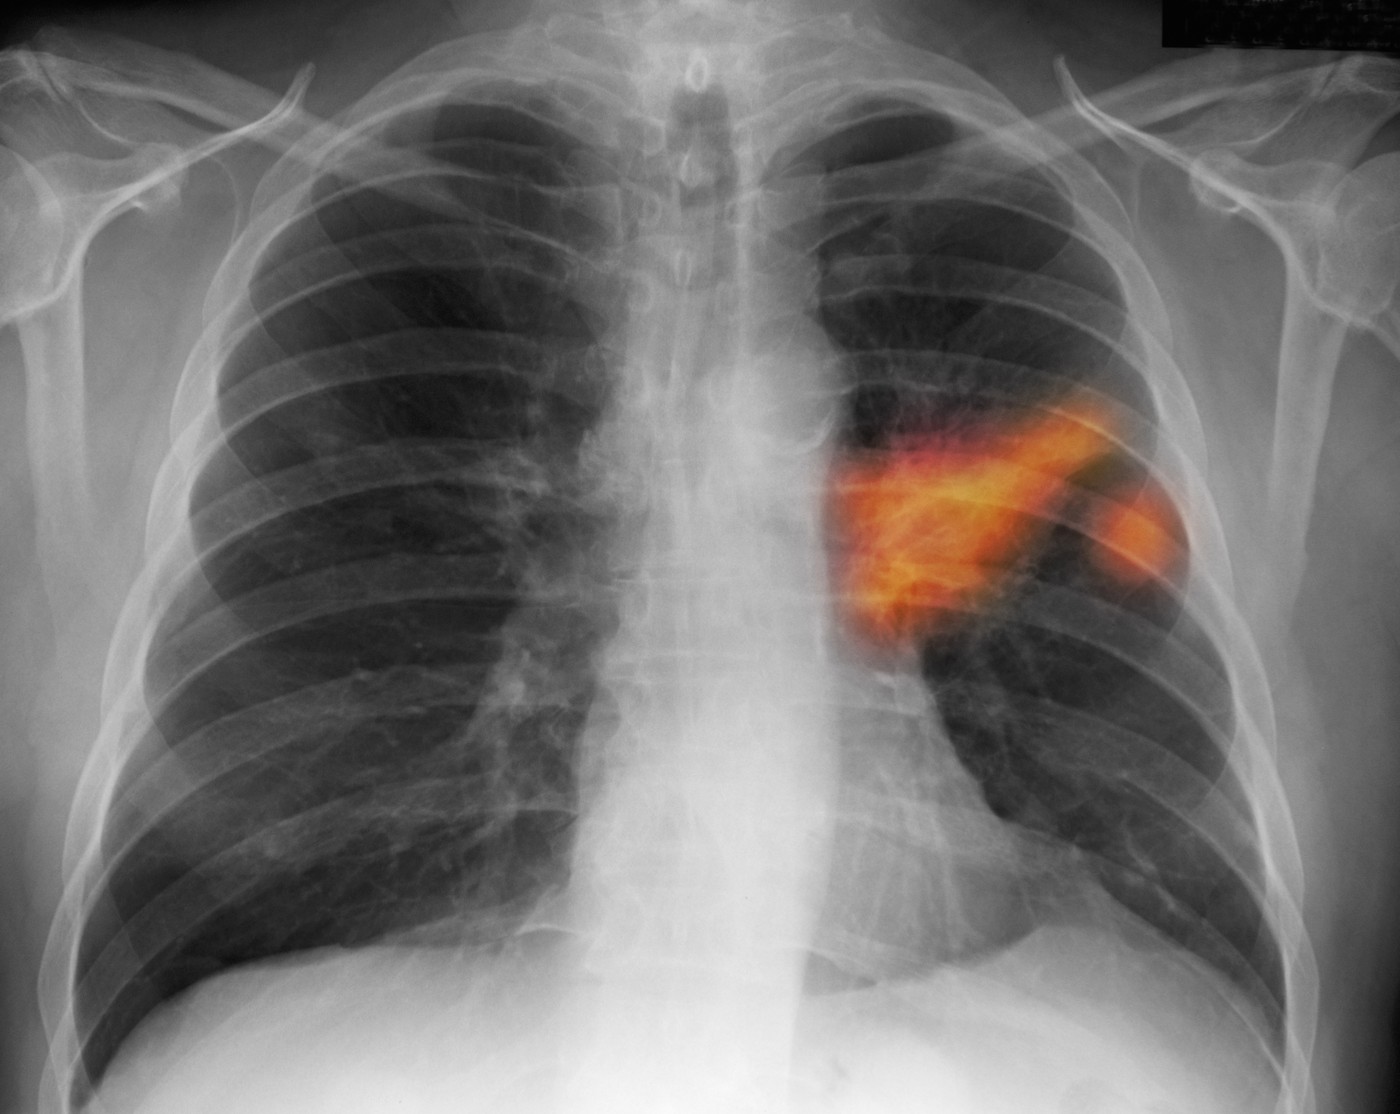

Pljučni rak je ena od oblik raka, ki se navadno odkrije zelo pozno, kar pomeni manj uspešno zdravljenje. Raziskovalci upajo, da bo nov urinski test to spremenil, poroča Guardian.

Razvili so namreč urinski test, ki bi lahko pomagal pri zgodnjem odkrivanju pljučnega raka. Zgodnejša diagnoza bi pomenila tudi zgodnejši začetek zdravljenja in večjo verjetnost za ozdravitev.

Pljučni rak je drugo najpogostejše rakavo obolenje na svetu po pojavnosti in najpogostejše po smrtnosti. V Sloveniji je po pogostnosti na tretjem mestu. Za to boleznijo zboli več kot 1.500 ljudi na leto, kažejo podatki ljubljanskega onkološkega inštituta